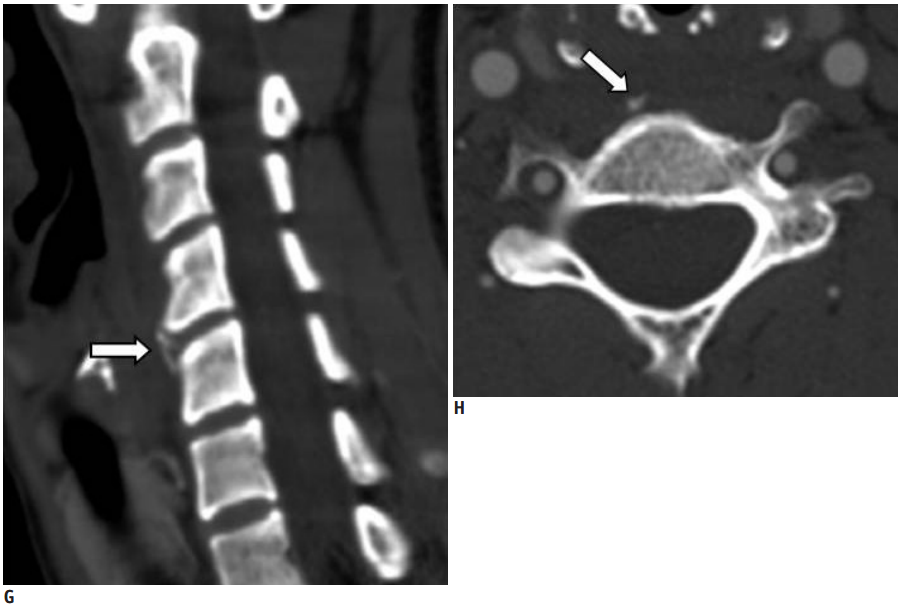

30岁女性,诊断为颈长肌钙化性肌腱炎,但钙化位于不寻常的位置:C4-5椎间隙前侧。A:颈椎侧位片示寰枢椎半脱位(长箭头)和椎前软组织肿胀(无线箭头);B,C和D:颈椎MRI示C1-6椎前软组织肿胀伴积液,D示齿状突骨侵蚀(无线箭头)

上述病人,E为增强,F为抑制像,G和H:经非甾体抗炎药治疗3天后查颈椎CT示C4-5椎前无定形钙化。

上述病人,I和J: 入院4天后复查颈椎MRI示椎前积液明显减少; K,随访2个月复查CT示C4-5前钙化灶减小。(PMID: 21852912)